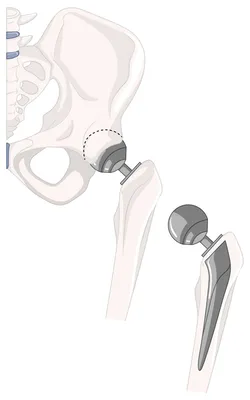

prothèse totale de hanche

Prise en charge et rééducation après prothèse totale de hanche (PTH) à Marseille – Cabinet MMK

La prothèse totale de hanche (PTH) est une intervention fréquente permettant de retrouver mobilité et confort de vie. Au cabinet MMK à Marseille 13006 (3 rue Saint-Jacques), nous proposons un programme de rééducation complet, progressif et personnalisé, pour accompagner chaque patient depuis les premiers jours postopératoires jusqu’au retour à l’activité.